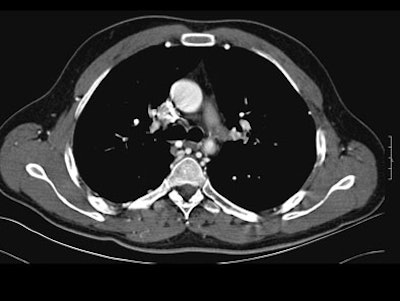

- On postcontrast axial CT images, there was significant narrowing of descending thoracic aorta distal to the origin of left subclavian artery, associated with adjacent collaterals and hypertrophied internal mammary arteries. [Figure 2]

| Figure 2. |